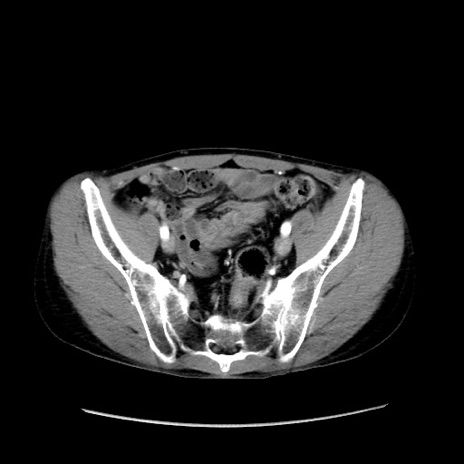

症例37(横断像)

【症例】40歳代 男性

【主訴】腹痛

【現病歴】4時間ほど前に電車に乗車中に臍部上より腹痛出現。徐々に増悪し起立困難となり、救急外来受診。生ものは数日食べていない。今朝お雑煮を食べた。

【身体所見】BT 36.8℃、BP 117/84mmHg、HR 91/min、SpO2 97%、苦悶様、腹部:臍上部広範囲圧痛あり、反跳痛±

【データ】WBC 8100、CRP 0.03